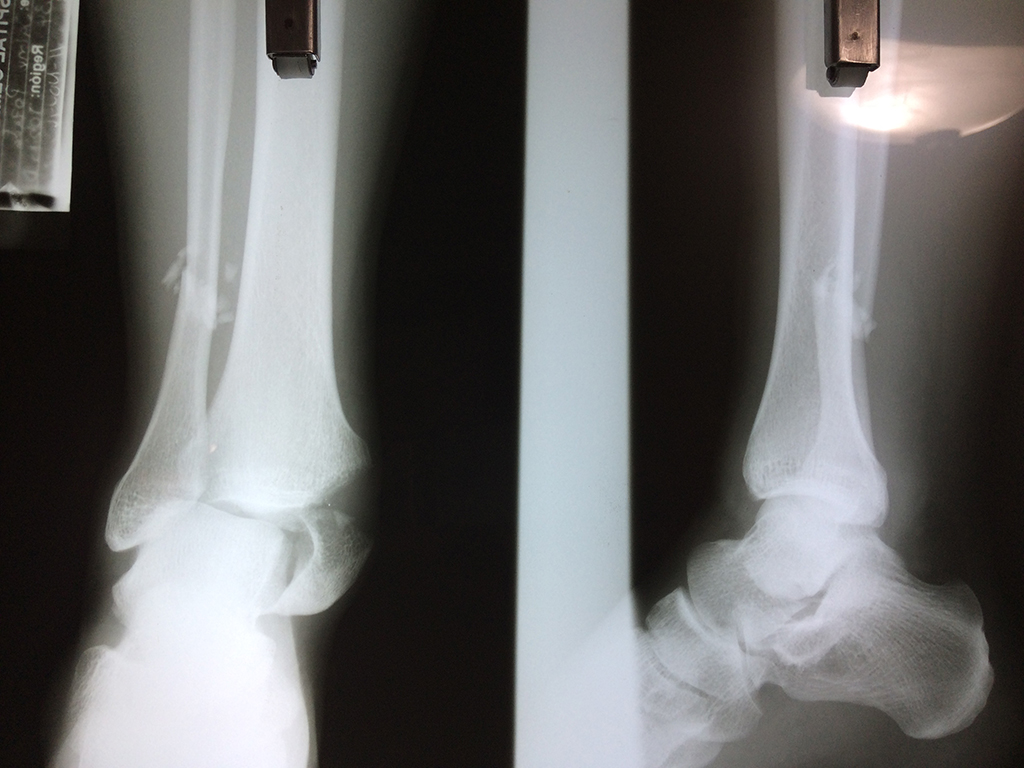

Una fractura de tobillo es la rotura de uno o más de los huesos del tobillo. Estas fracturas pueden ser:

Algunas fracturas de tobillo pueden requerir cirugía si:

- Los extremos de los huesos están desalineados entre sí (desplazados).

- La fractura se extiende hasta la articulación del tobillo (fractura intra-articular).